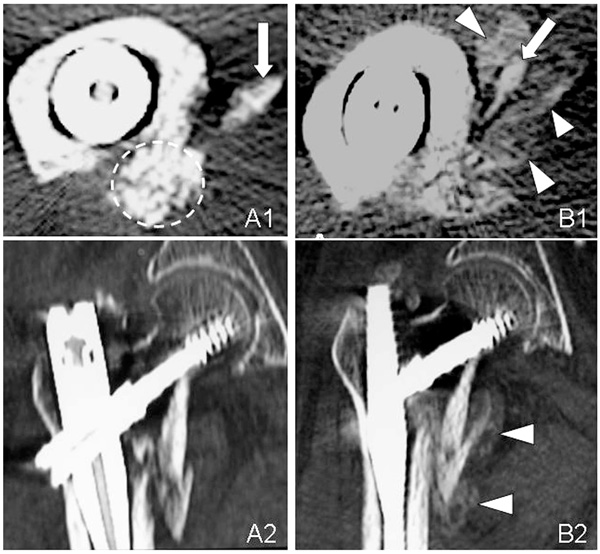

Axial (A1, B1) and sagital (A2, B2) CT images of the unstable intertrochanteric fracture in Case 1. The complex of β-TCP granules, hyaluronate, and rhFGF-2 remains in its original place (broken circle) at 3 weeks (A1). CT image shows marked new bone formation at 6 weeks (B1, B2). The arrows point to the lesser trochanter and arrow heads point callus.

CT Evaluation of 3, 8, and 12-week Bone Replacement

At 3 weeks, CT scan images revealed callus formation in only 3 cases. β-TCP granules remained in their original locations and were still visible (Figs. 4A1, 4A2, 5, and 7A). CT scans taken at 6 or 8 weeks showed that most β-TCP granules were resorbed, and new bone formation was found in all cases (Figs. 4B1, 4B2, 5, and 7B). At 12 weeks, β-TCP granules were replaced by bone and marked new bone formation was observed in all cases. Bridging between the shaft and the displaced lesser trochanter was developed in 24 cases. Bridging did not occur in one case due to poor location of the injection (Fig. 7C).